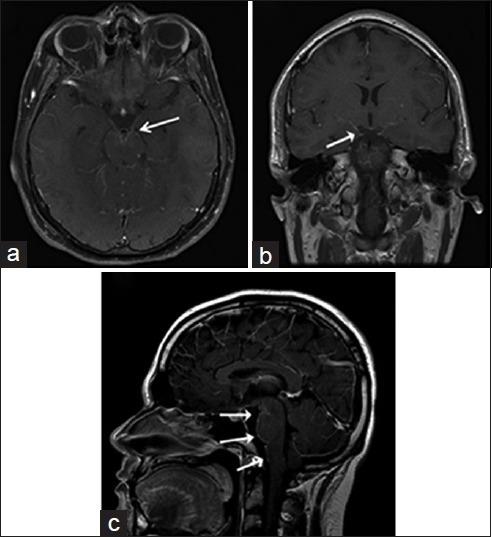

中枢神经系统真菌感染:图文综述

Fungal Infections of the Central Nervous System: A Pictorial Review.

Fungal infections of the central nervous system (CNS) pose a threat to especially immunocompromised patients and their development is primarily determined by the immune status of the host. With an increasing number of organ transplants, chemotherapy, and human immunodeficiency virus infections, the number of immunocompromised patients as susceptible hosts is growing and fungal infections of the CNS are more frequently encountered. They may result in meningitis, cerebritis, abscess formation, cryptococcoma, and meningeal vasculitis with rapid disease progression and often overlapping symptoms. Although radiological characteristics are often nonspecific, unique imaging patterns can be identified through computer tomography as a first imaging modality and further refined by magnetic resonance imaging. A rapid diagnosis and the institution of the appropriate therapy are crucial in helping prevent an often fatal outcome.

中枢神经系统(CNS)真菌感染对免疫功能低下的患者构成威胁,其发病主要取决于宿主的免疫状态。随着器官移植、化疗及人类免疫缺陷病毒感染病例的增多,作为易感宿主的免疫功能低下患者数量不断增加,中枢神经系统真菌感染也更为常见。它们可能导致脑膜炎、脑炎、脓肿形成、隐球菌瘤及脑膜血管炎,疾病进展迅速且症状常相互重叠。尽管影像学特征通常不具有特异性,但计算机断层扫描作为首选成像方式可识别出独特的影像模式,磁共振成像则可进一步完善。快速诊断并采取恰当治疗对于预防往往致命的后果至关重要。